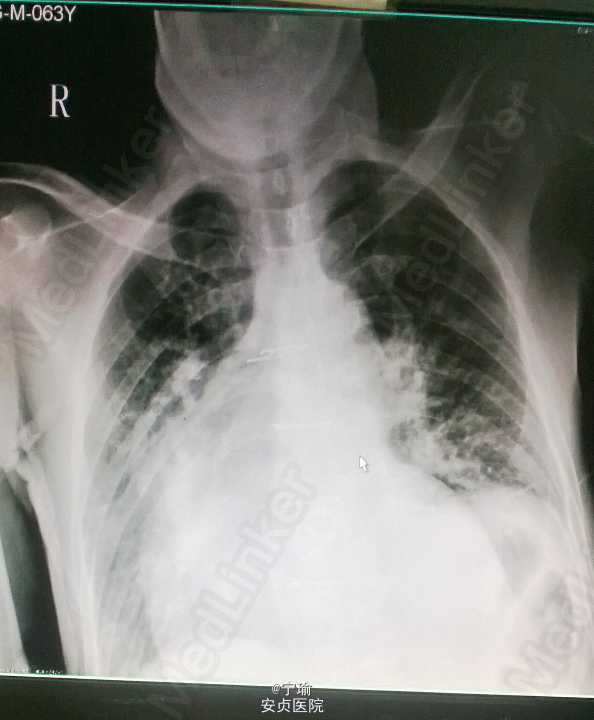

查体——体温36℃,脉搏110次/分,呼吸18次/分,血压137/95mmHg。神志清楚,精神状态较差,半卧位,急性痛苦病容,表情痛苦。前正中线可见一自胸骨上窝至剑突纵行手术疤痕,另可见一平行于第5肋上缘水平疤痕与纵行疤痕相连。双肺呼吸运动对称,肋间隙未见异常,双侧语颤对称。双肺呼吸音粗,可闻及呼气末少量哮鸣音、少量湿罗音。心前区无隆起,心界向两侧扩大,心率125次/分,心律绝对不齐,第一心音强弱不等,未闻及早搏。二尖瓣区闻及机械瓣关闭音。双下肢无水肿。余查体无异常。 辅查——血常规:白细胞计数18.05G/L,中心粒细胞计数14.64G/L。BNP 10804ng/l,血沉27mm/h,PCT 0.28ug/l,肾功能正常。胸片(图1):两肺肺水肿征,心影扩大。心脏彩超(图2):左室心肌收缩普遍减弱,EF30%,双房及左室腔增大,二尖瓣人工瓣膜表面毛糙,前瓣活动,后瓣未见明显活动,二尖瓣口CDFI检出舒张期两股血流,建议食道超声进一步检查明确。颈动脉彩超:双侧颈动脉内膜粗糙增厚,右侧壶腹部附壁斑块形成。抽血送血培养。